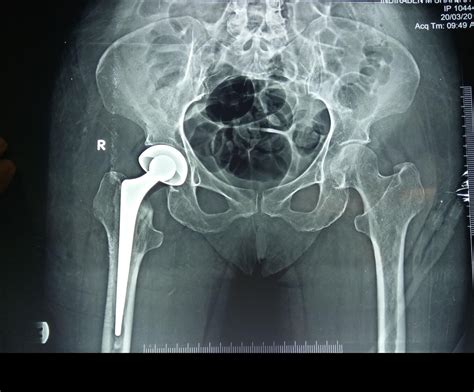

Conversely, if the fracture is severe or if the blood supply to the femoral head has been disrupted, a hip replacement may be necessary. In a partial hip replacement, only the head of the femur is replaced with a metal prosthesis. In a total hip replacement, both the head of the femur and the socket in the pelvic bone are replaced. This procedure is generally preferred for active older adults as it provides better long-term outcomes and reduces the risk of needing follow-up surgeries.

Total Hip Replacement Severe fractures or pre-existing arthritis Replaces both femoral head and the pelvic socket